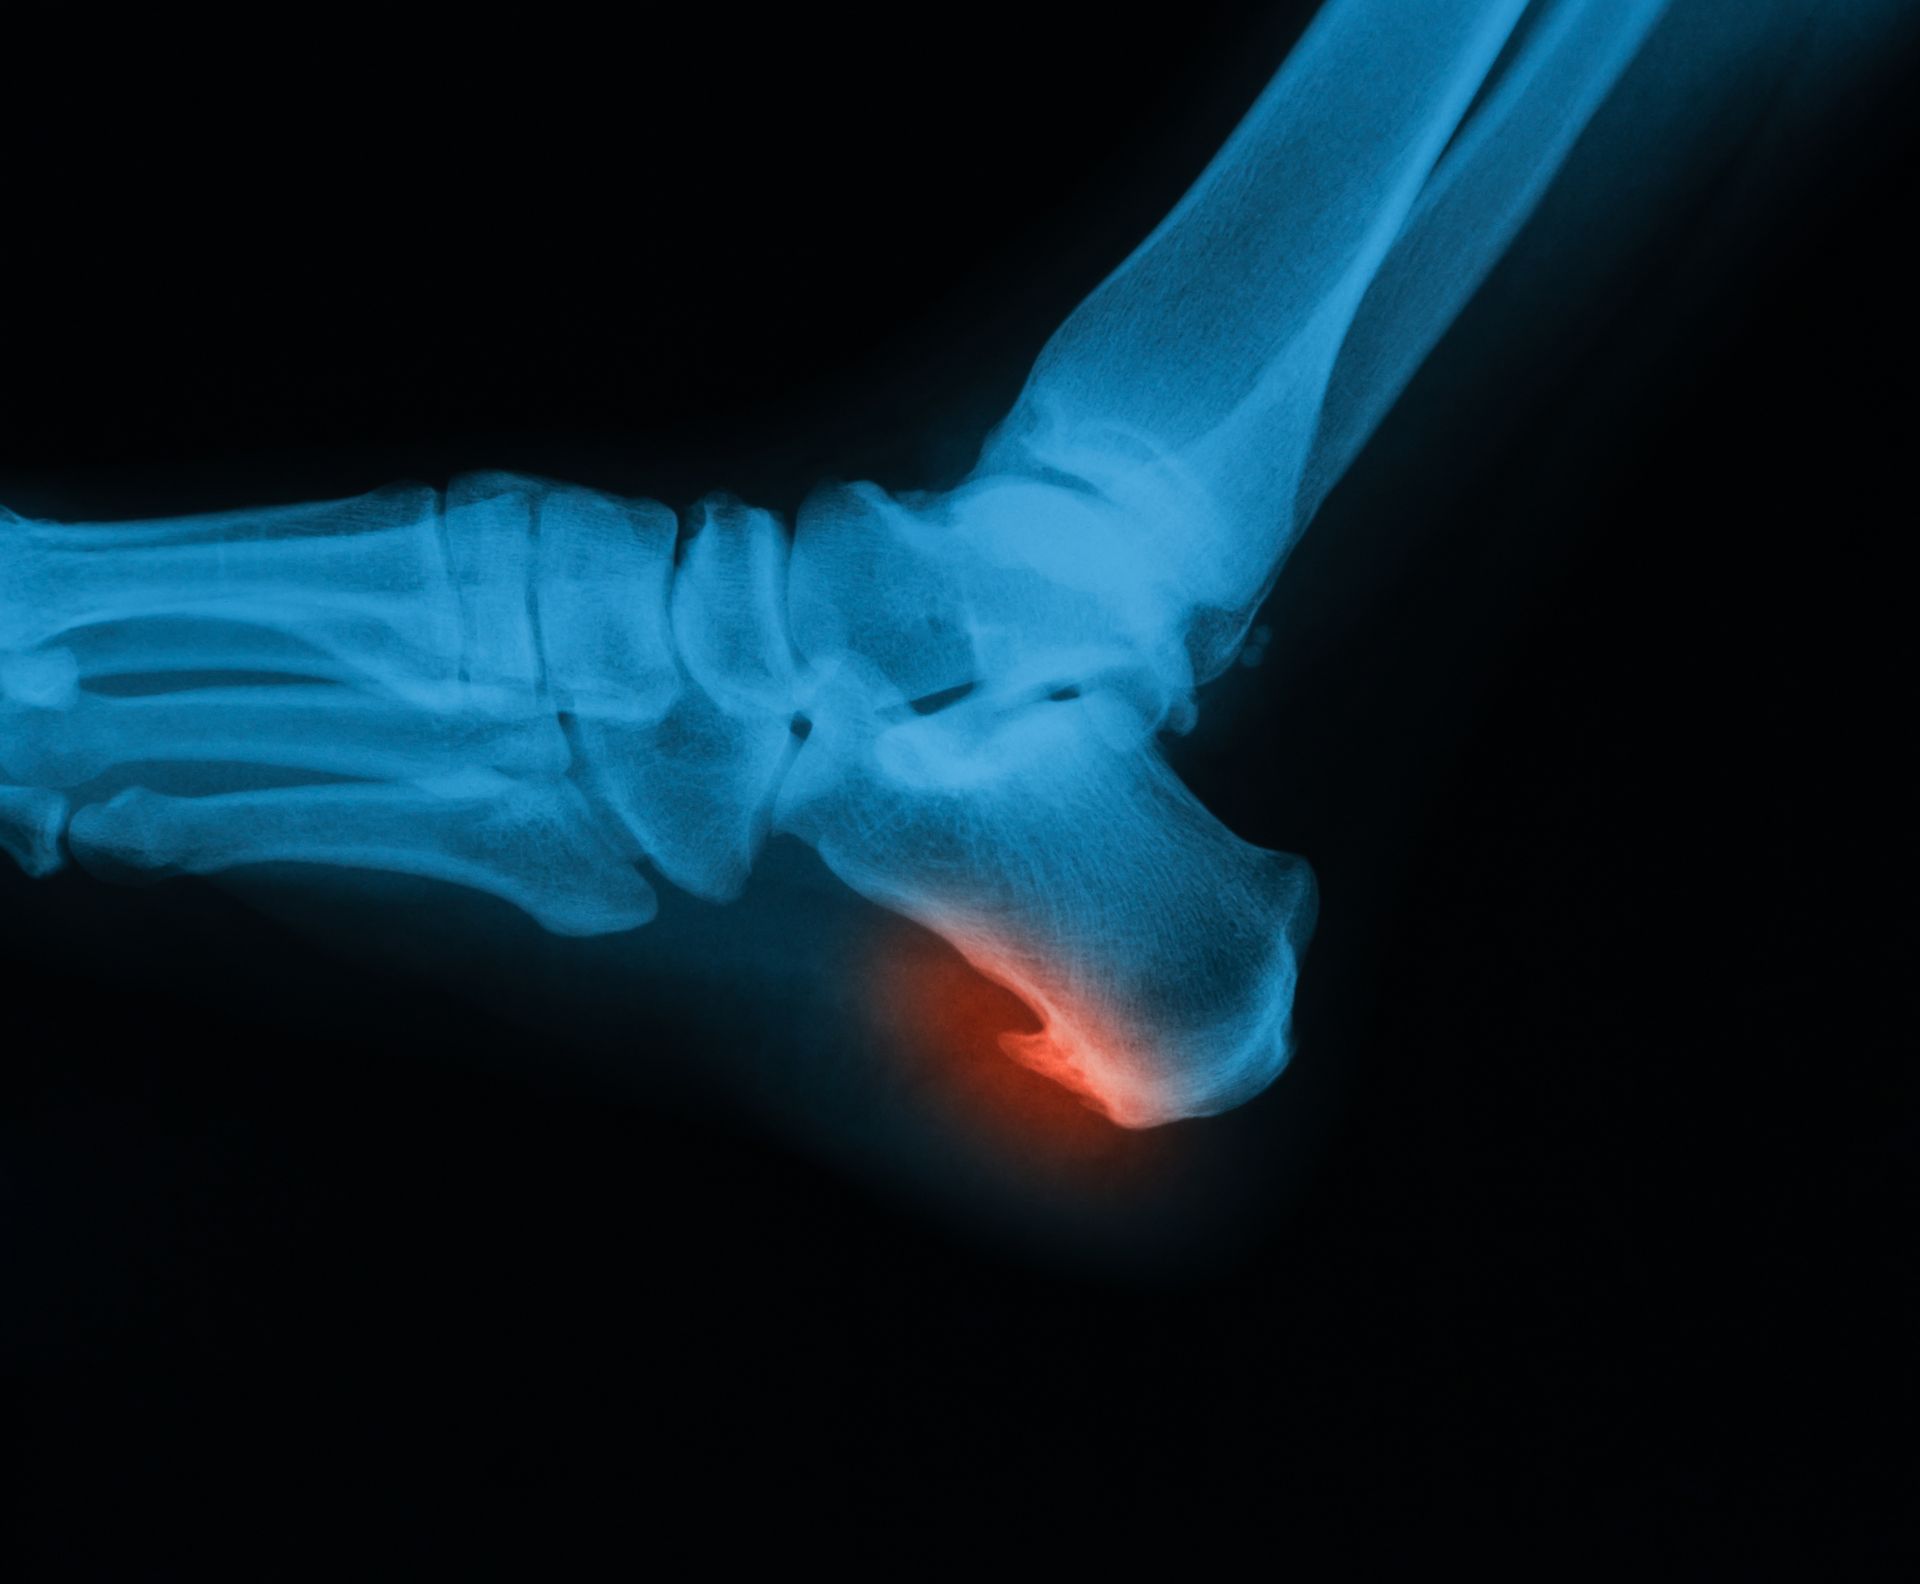

Podiatric medicine focuses on diagnosing and treating conditions of the foot, ankle, and lower leg. Podiatrists provide thorough exams, accurate diagnoses, and effective treatments. They can prescribe medications, create custom orthotics, perform surgery when needed, and offer guidance on footwear, exercise, and preventive care to support long-term foot and ankle health.